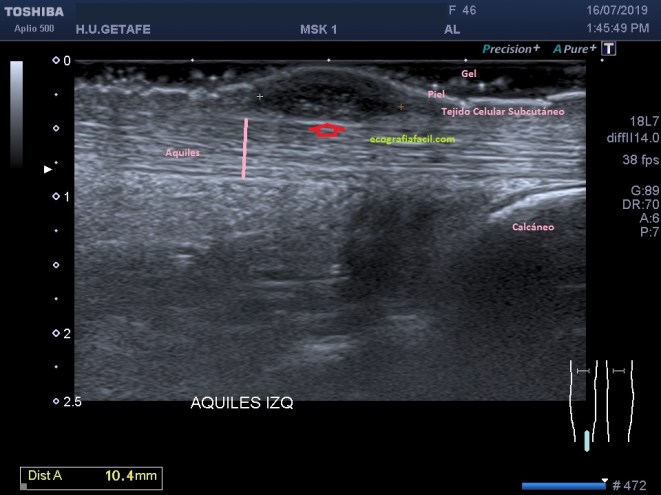

Sonda lineal de alta frecuencia, paciente tumbada en decúbito prono, pies colgando al final de la camilla. Flexión dorsal del pie con el aquiles afectado.

La exploración del Aquiles estándar en este caso revela un aquiles perfectamente normal, hiperecogénico, sin aumento de calibre. Existe a cinco centímetros de la inserción una lesión ovoidea, superficial, heterogénea, extramuros del Aquiles, justo debajo de la piel, dolorosa, no capta señal doppler. Grasa de Kager conservada.

La lesión no comprime al tendón y es compresible. Imagen 8.

En la imagen número 1 podemos ver una imagen bastante habitual en el estudio del aquiles, marcado con flecha roja, vemos una zona de hipoecogenicidad que corresponde al cambio de angulación de las fibras que en la zona de inserción se objetivan claramente hipoecogénicas en relación con anisotropía.